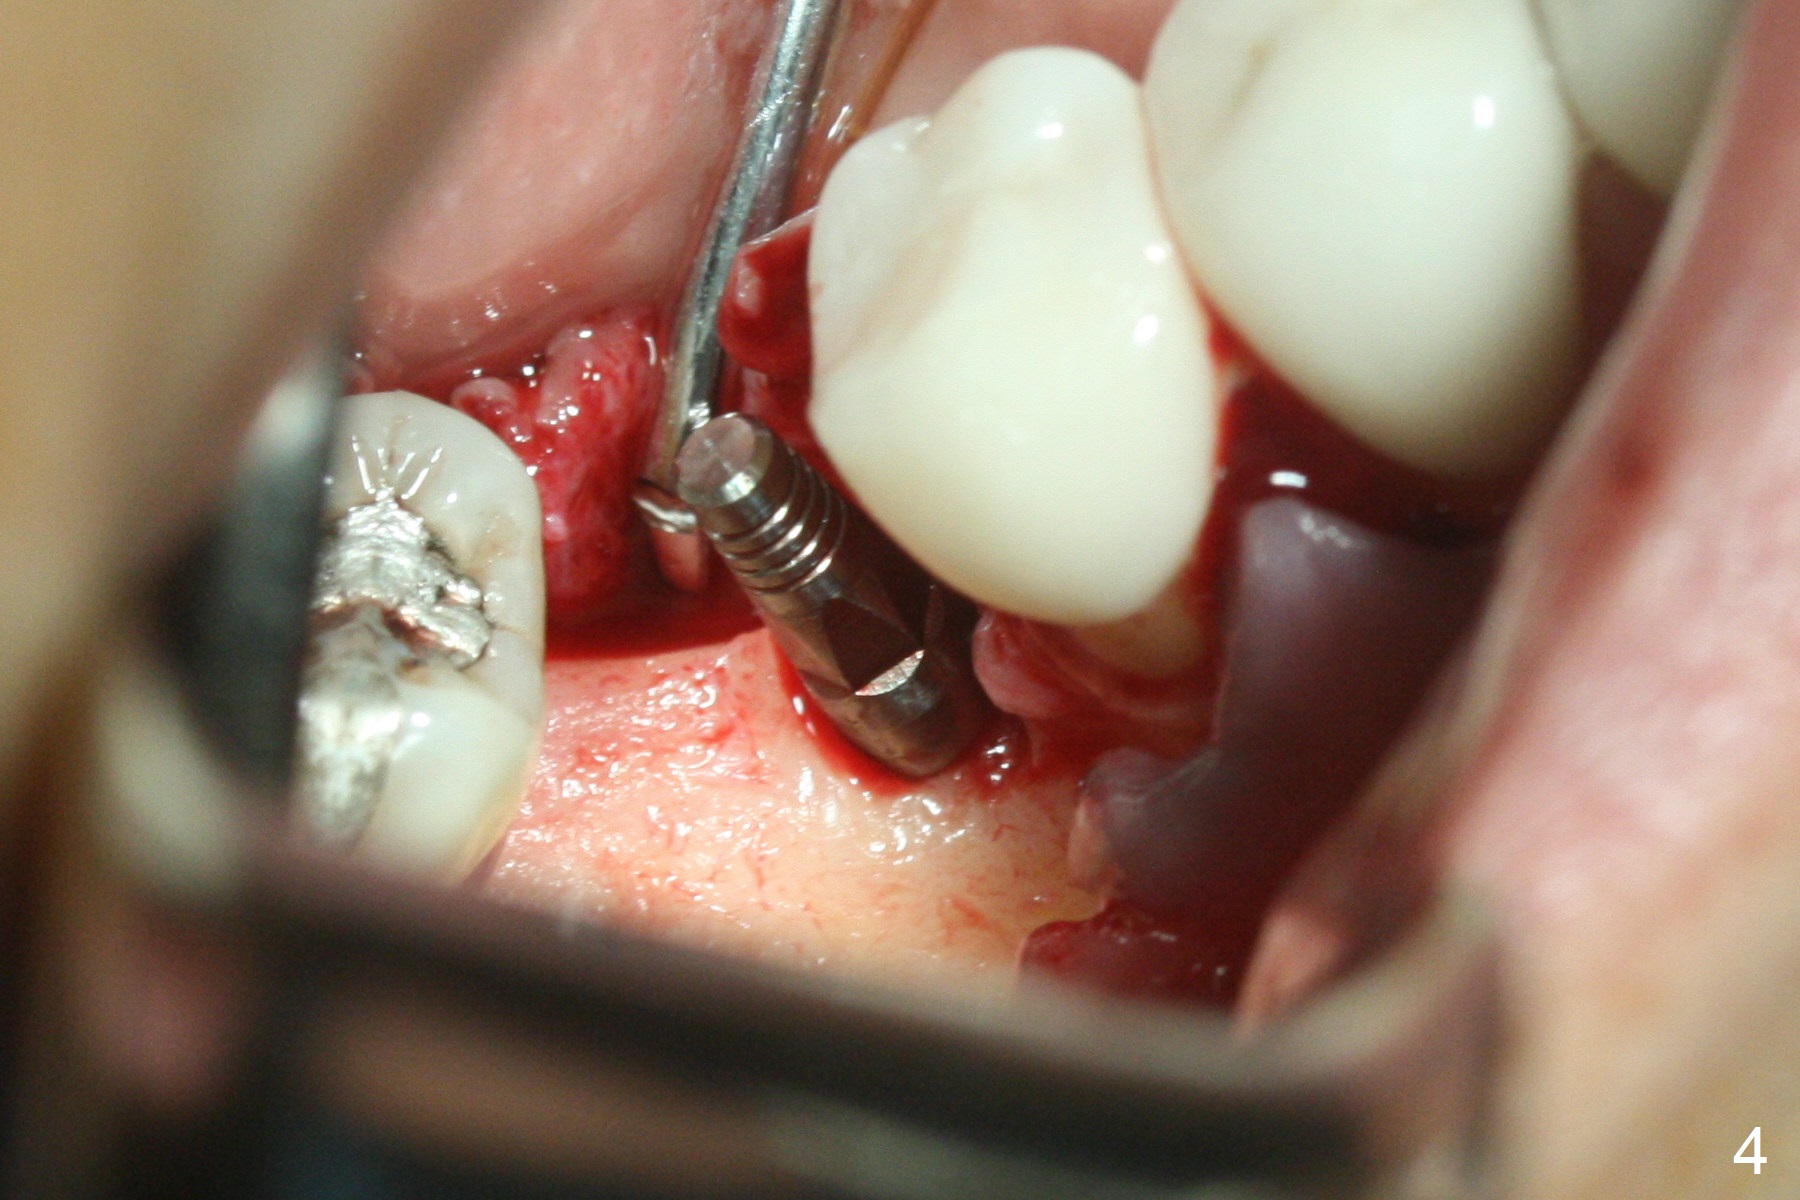

Incision reveals a narrow ridge and a narrow mesiodistal space at #30 (Fig.1).  It seems that a 1-piece implant is indicated.  Due to limited mouth opening, a 1.2 mm drill is unstable in place after use for 10 mm; instead a 1.5 mm drill is able to be inserted for 8 mm (Fig.2).  A 3x10(2) mm 1-piece dummy implant is placed with 40 Ncm at an apparently acceptable level (Fig.3 >).  Clinically a few threads are exposed buccally.  When a definitive implant with the same dimension is inserted with 45 Ncm, it looks seated too deep (Fig.4,5).  The latter is noted after suturing.  The implant is backed up for a few turns so that the length of the abutment appears a little more reasonable.  Introspectively, a 4 mm cuff should have been used after ridge reduction.  Although there is no bone loss 4 months postop (Fig.6), the abutment margin (Fig.7 arrow) is subgingival (red dashed line: gingival margin).  Diode laser is used for gingivectomy prior to impression.  The bone density around the implant increases 11 months post cementation (Fig.8 *), probably related to recurrent #18 infection.  The patient uses floss after meal.